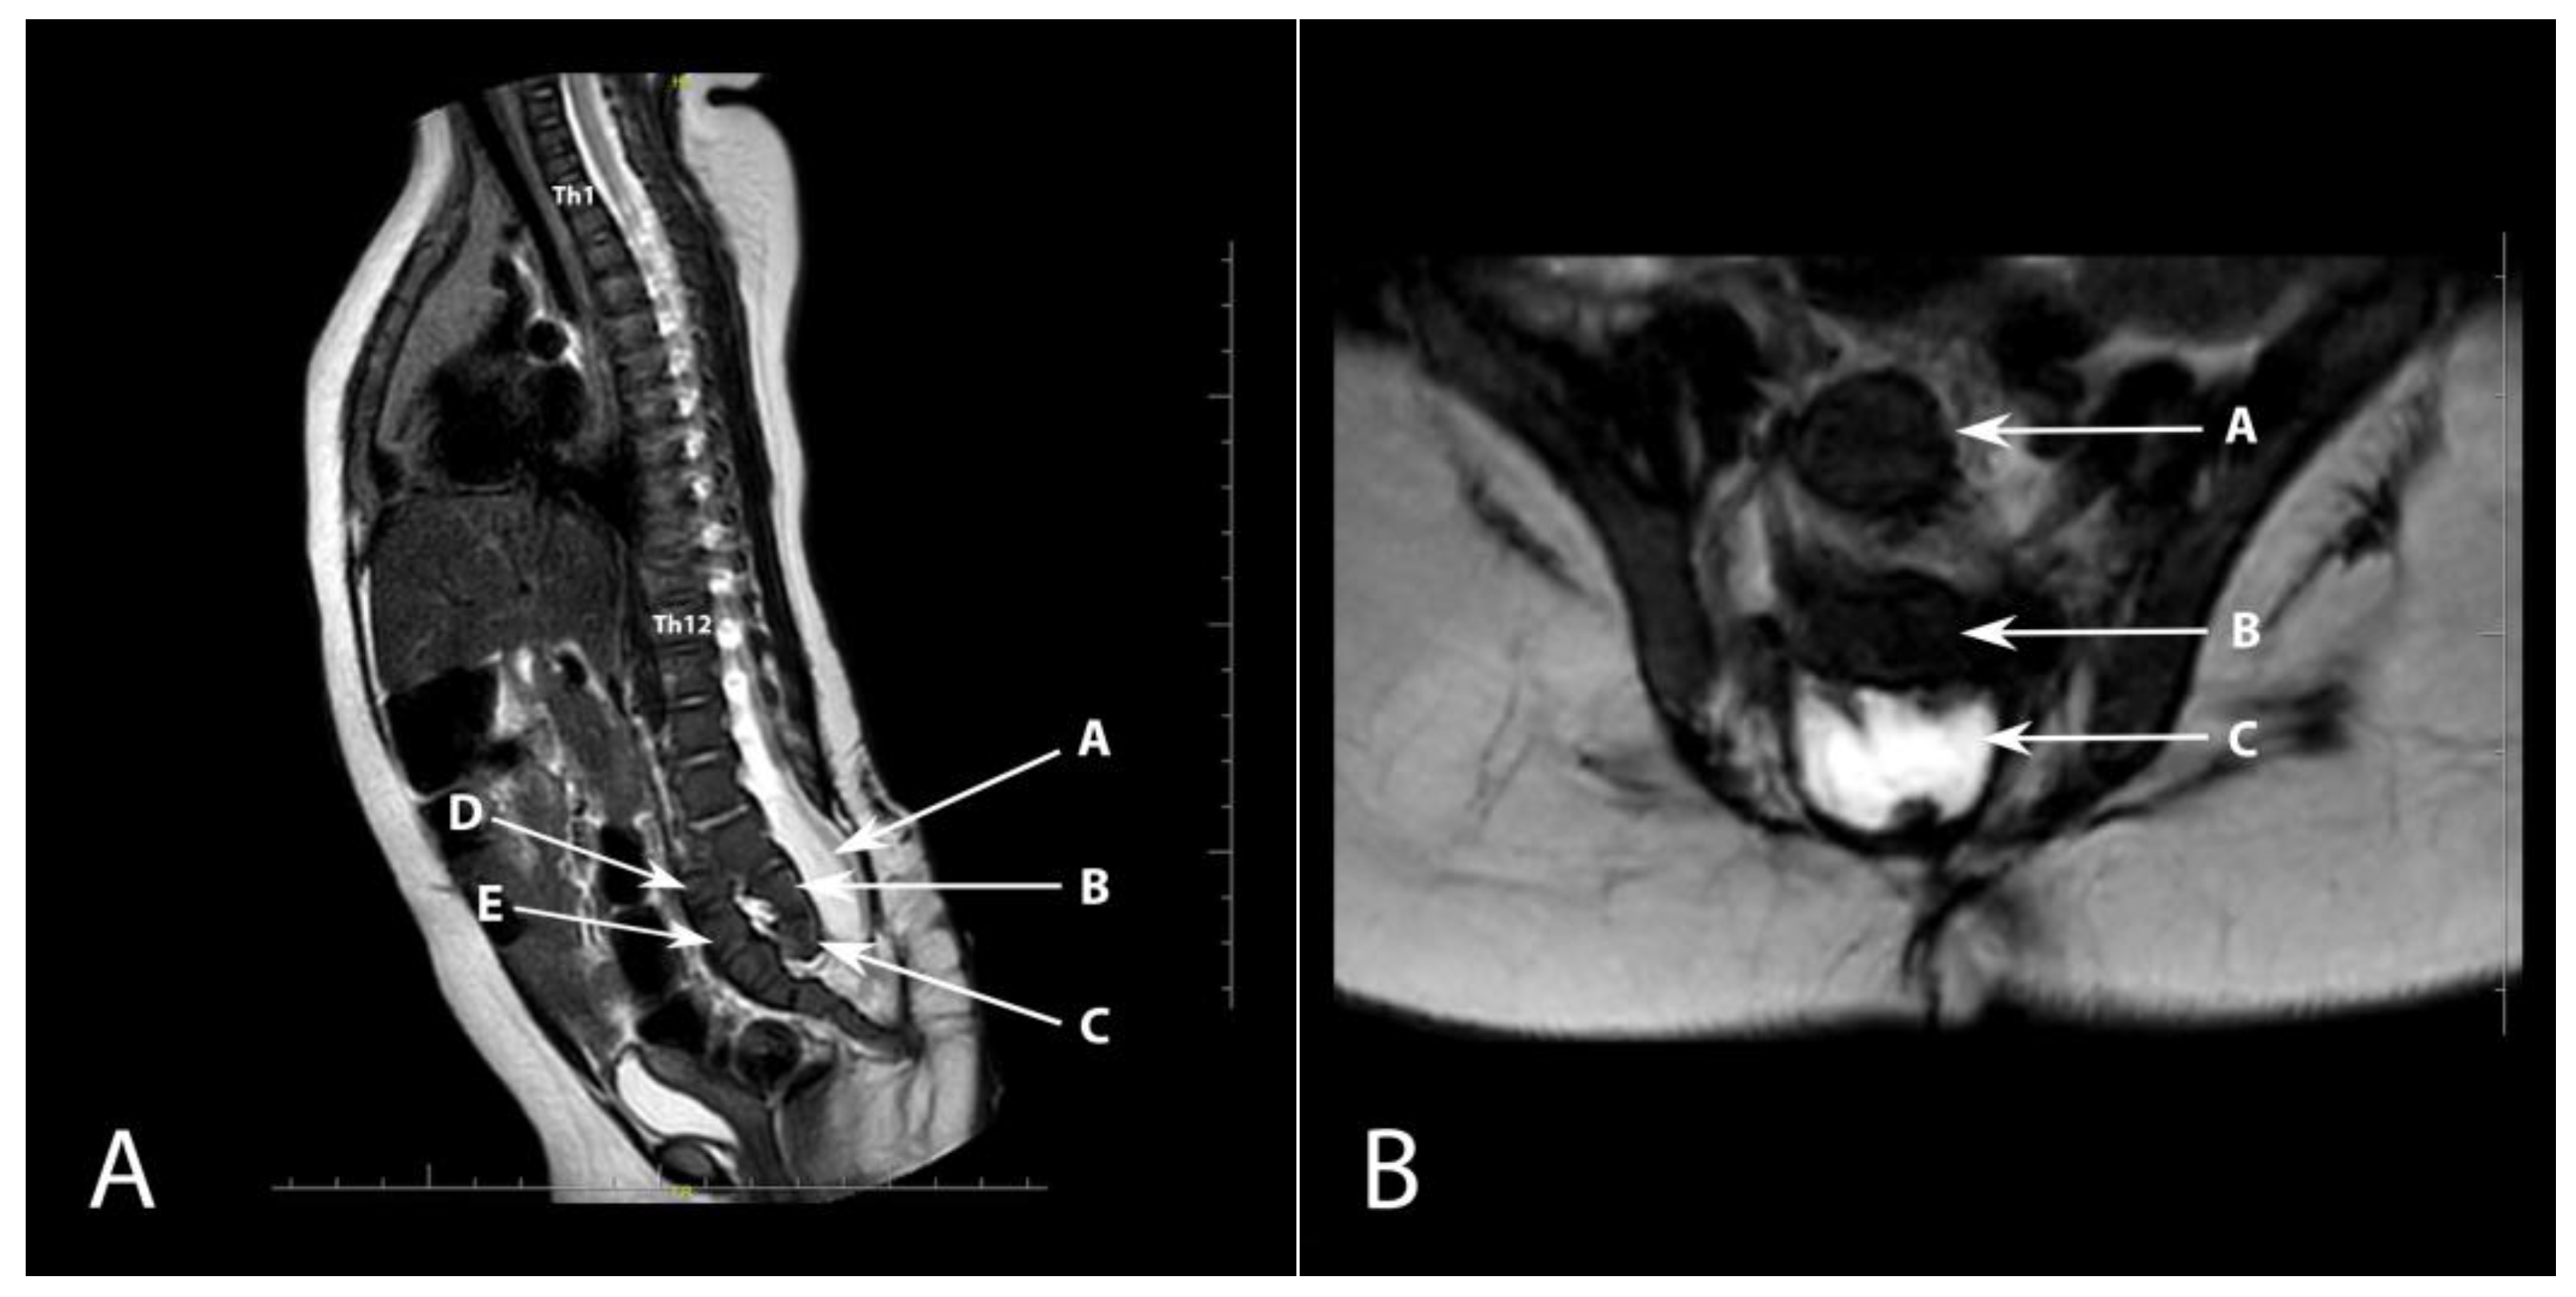

Congenital Anterior Dislocation of the Sacrococcygeal Bone in a Newborn